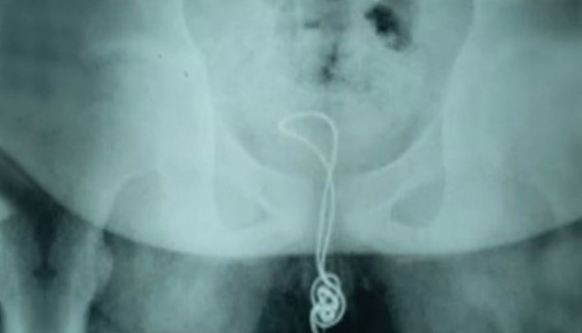

İlginç olay Çin'de yaşandı. 13 yaşındaki bir erkek çocuğun cinsel organına USB kablosu sıkıştı ve düğümlendi. Kabloyu geri çekemeyen çocuk, acı içinde hastaneye kaldırılıp ameliyata alındı.

ÇIKARAMAYINCA AİLESİNE SÖYLEMEK ZORUNDA KALDI;Adı açıklanmayan Çinli çocuk, cinsel organından içeri soktuğu kablonun mesanesinin içinde düğüm olması üzerine geri çıkaramadı. Yaklaşık 20 santimetrelik kablo yüzünden dayanılmaz derecede acı çeken çocuk, durumu ailesine söylemek zorunda kaldı.

MESANESİNİ KESEREK ÇIKARDILAR; Çin'in kuzey-doğu Heilongjiang eyaletindeki Linkou şehrindeki bir hastaneye kaldırılan çocuğun içinde düğümlenen kabloyu doktorlar da dışarı çıkarmayı başaramayınca tek çare olarak ameliyata alındı ve kablo mesanesinden çıkarıldı.